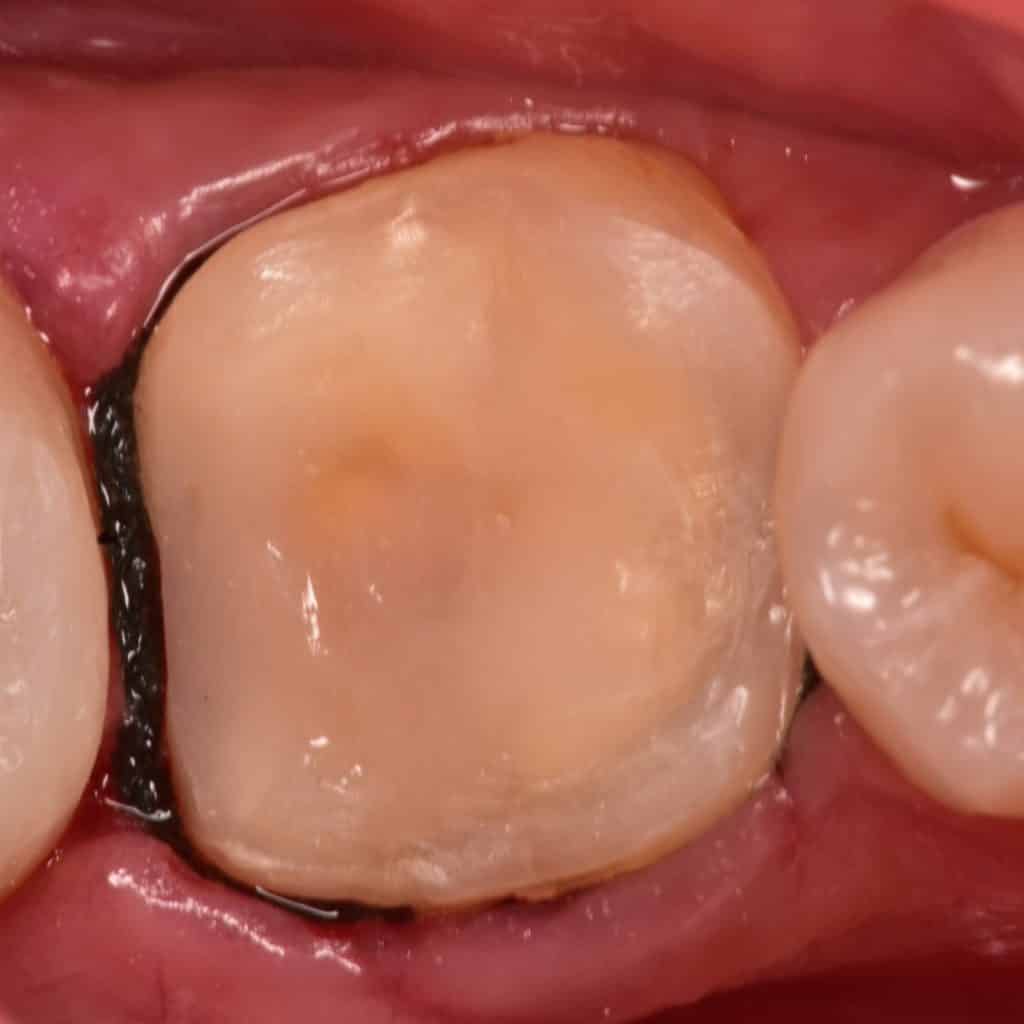

Initial situation showing large defective composite filling

During Old composite removal you can see the liner this type of liner have weak adhesion to dentin and so post operative sensitivity will occur, the best liner under composite is the bond itself

You can see the liner below the old composite ,irregular margins, mesial wall of the second molar need to be restored

Here you can see that the remaining walls are weak and must reduced and replaced by strong indirect lithium disilicate overlay

In cementation day , Isolation done